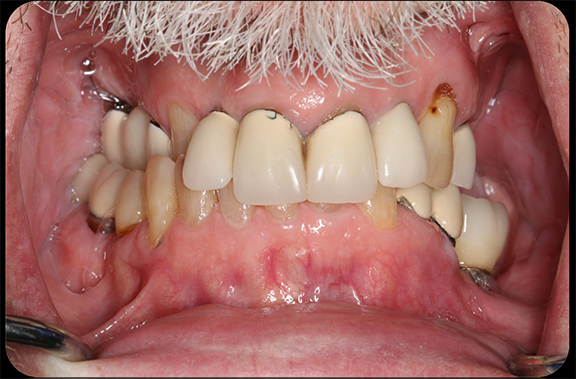

In a more complicated case, often there are more complicated starting points. The patient shown in Figure 8 had bite posture problems, caries, periodontal disease, failing restorations and implants, and a history of head-and-neck cancer. Such a patient may logically fear the unknowns of treatment, but with the treatment planning and rendering capabilities robotics provide, the practitioner could determine exactly what the patient needed, convey the information to the patient, and deliver promised results.

Fig 8. The patient had bite posture problems, caries, periodontal disease, failing restorations and implants, and a history of head-and-neck cancer.

Figure 8